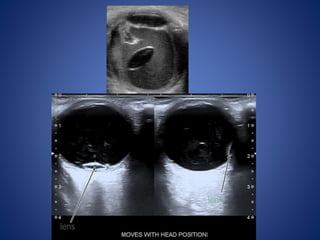

Partially dislocated lens

• #11 dislocated or luxated to the dependent part of the patients eyeball, close to the retina